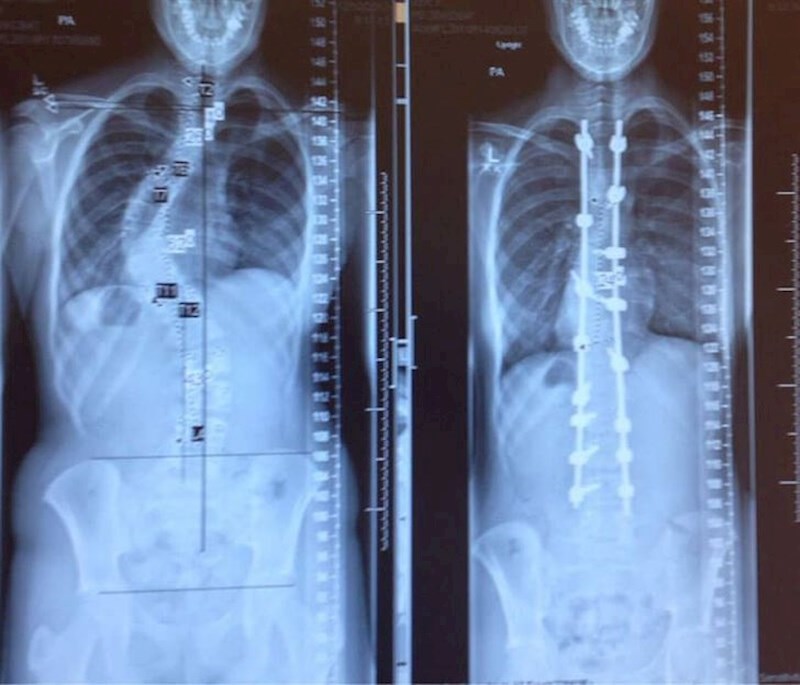

Rendgenska snimka prije i nakon operacije ispravljanja skolioze